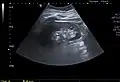

The complex cyst can be further evaluated with doppler ultrasonography, and for Bosniak classification and follow-up of complex cysts, either contrast-enhanced ultrasound (CEUS) or contrast CT is used.[12]